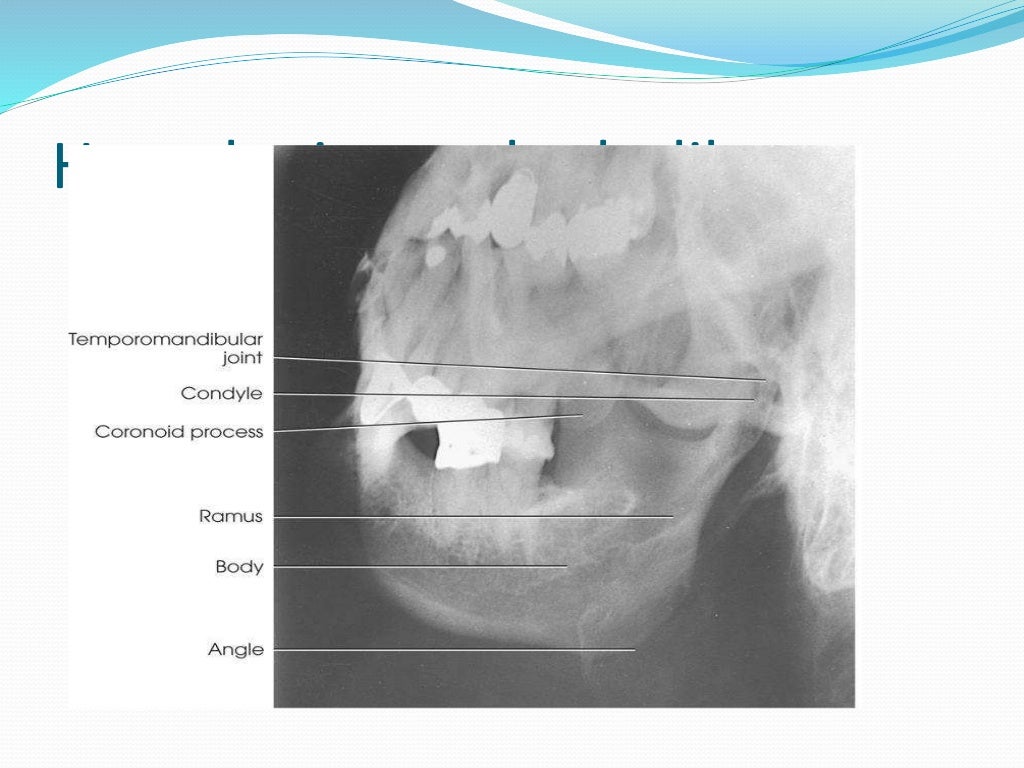

Mandible X Ray Views . Learn how to position the patient and the part for various projections of the face and mandible, such as pa, lateral, oblique, and intraoral views. Radiopaedia.org provides a comprehensive series of normal mandible radiographs for educational and reference purposes. The body and ramus can be viewed along with the tmj articulation. The occipitomental (om) 4 or waters view or parietoacanthial projection 2 is an angled pa radiograph of the skull, with the patient gazing slightly upwards. Radiography represents the first level imaging technique in patients with traumatic injury of the mandible. The mandible consists of the horizontal arch, containing the teeth and the ascending arch (ramus) with the hinge joint at the. A lateral view can be helpful if an opg cannot be obtained.